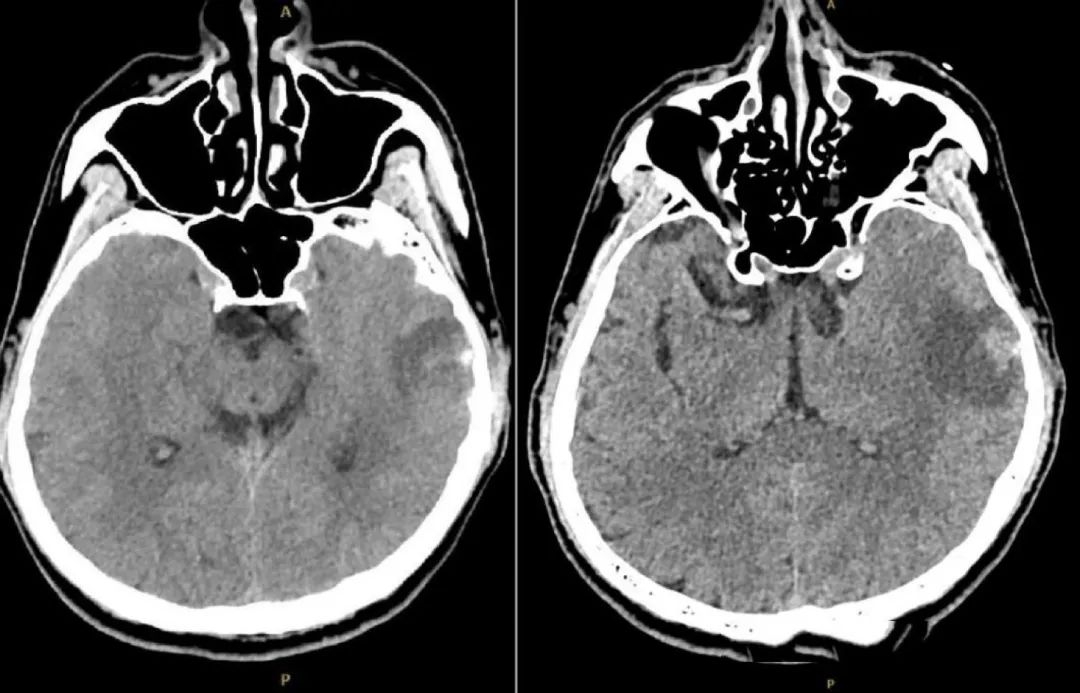

图1. 头颅CT(发病后1周):左侧颞叶血肿可能。

经检查,刘同学的大脑状态在短时间内急剧恶化,多处脑出血和肿胀、头颅CT血管影像中很多静脉血管消失。

经医生确诊,刘同学患的是一种特殊脑梗,致死率可以高达30%~40%,是普通脑梗死亡率的3倍以上!